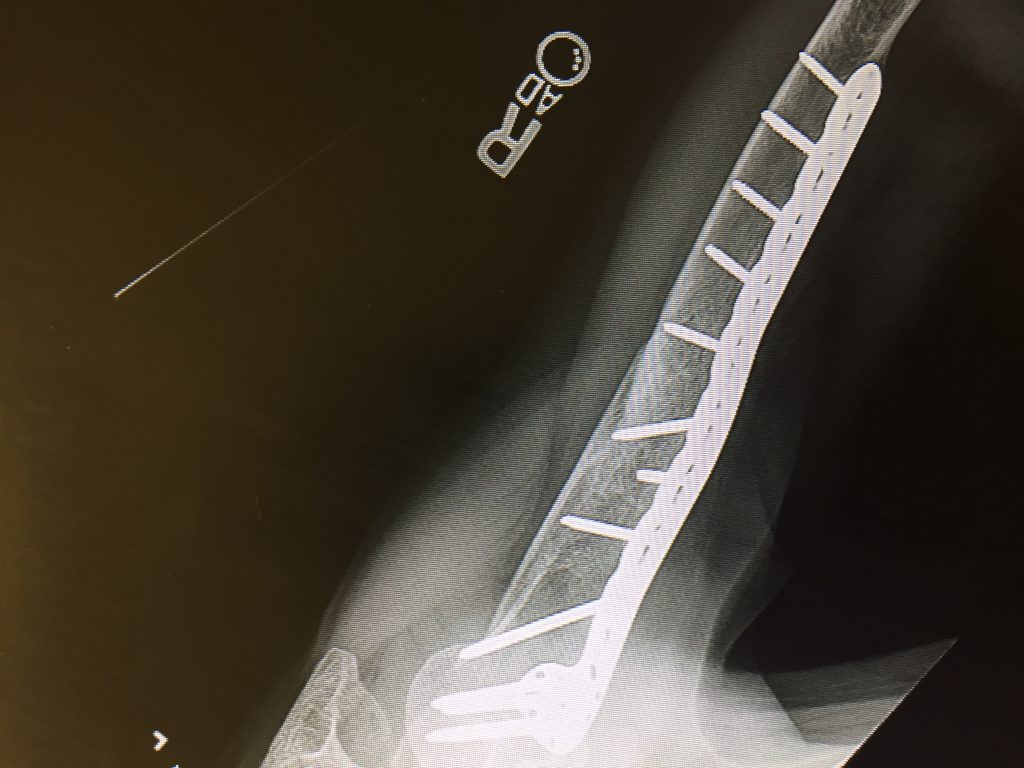

The most amazing hospital and the most amazing surgeon. After a year of seeing 5 different doctors, Dr. Wellman performed the surgery and rebuilt my severely broken and shattered humerus. The pictures speak for themselves. WHAT SCAR?!